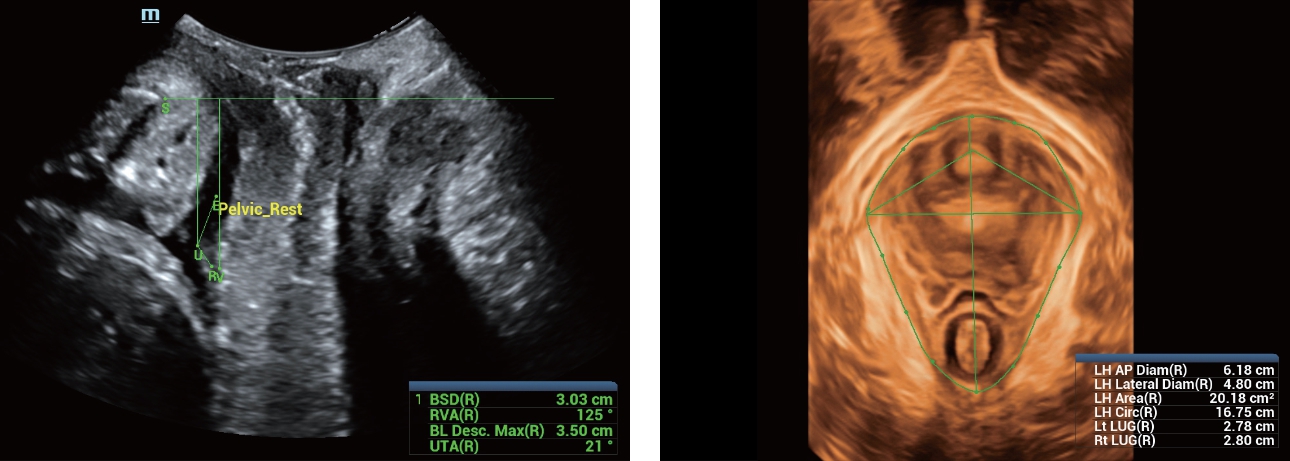

Fin dalla sua fondazione Mindray esplora continuamente nuovi modi per migliorare l'affidabilit├Ā diagnostica. Equipaggiata con la pi├╣ rivoluzionaria tecnologia ZONE Sonography?, la nuova piattaforma ZST+ di Resona 7 porta la qualit├Ā dell'immagine ecografica ad un livello superiore con l'acquisizione per zone e l'elaborazione dei dati canale.

Oltre alla qualit├Ā delle immagini di livello eccellente, Resona 7 migliora anche le capacit├Ā di ricerca clinica il rivoluzionario V Flow per la valutazione emodinamica vascolare, e l'acquisizione piani pi├╣ intelligente dal set di dati 3D per la diagnosi del sistema nervoso centrale fetale. Combinando il pi├╣ intuitivo funzionamento multi-touch basato su gesti e tutte le caratteristiche cliniche essenziali, Resona 7 sta veramente portando nuove tendenze nellŌĆÖinnovazione dellŌĆÖecografia.